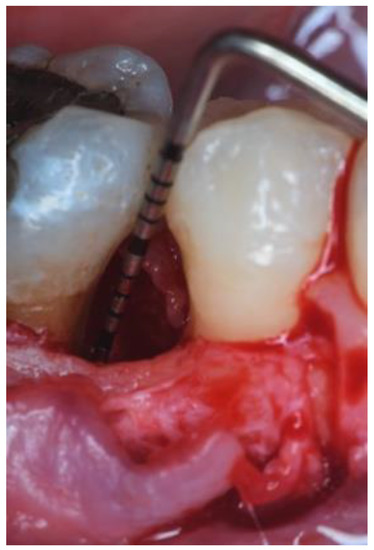

2. Case Series

2.3. Therapeutic Intervention